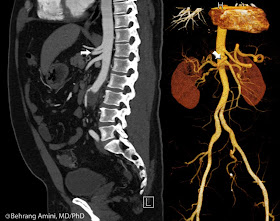

The patient shown here had tricuspid atresia, for which he had a unidirectional Glenn procedure when he was 2 and a modified Fontan when he was 13, followed by a stent of the Hancock conduit in his 20s. The unidirectional Glenn can be seen in the top pair of images, showing a direct connection between the superior vena cava and the right pulmonary artery. The bottom image pair shows the second stage of the procedure, with diversion of inferior vena caval blood into the left pulmonary artery via a Hancock conduit. Multiple clipped pulmonary arteriovenous malformations are seen.